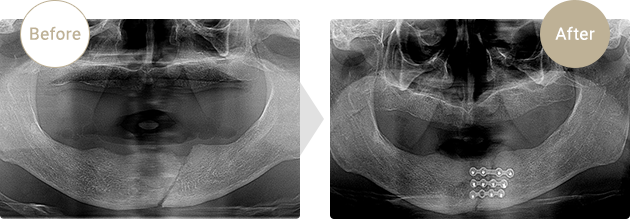

症例.01

下顎骨骨折

自転車運転中に転倒、下顎を強打下顎骨観血的整復術にてチタンプレートで固定しました。